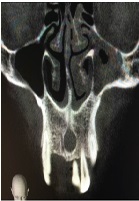

Evaluation of CBCT Images: Two Case Reports of Calcifications and Anatomical Variations

Hilal Peker Ozturk, Kaan Gunduz, Seda Ozgedik, Umit Karacayli, Hakan Avsever*, Kaan Orhan